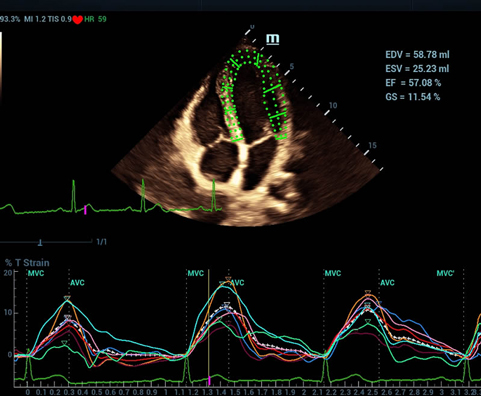

Sejak didirikan, Mindray terus mencari cara baru untuk meningkatkan keandalan diagnostik. Didukung Teknologi ZONE Sonography? terkini, platform ZST+ baru Resona 7 meningkatkan kualitas gambar ultrasound melalui pengambilan zona dan pemrosesan data saluran.

Selain kualitas gambar premium, Resona 7 juga meningkatkan kemampuan penelitian klinis dengan V Flow revolusioner untuk evaluasi hemodinamika vaskular, serta pengambilan penampang tercanggih dari rangkaian data 3D untuk diagnosis CNS pada janin. Kombinasi pengoperasian multisentuh berbasis gerakan yang paling intuitif dengan semua fitur klinis penting membuat Resona 7 menjadi gebrakan baru dalam inovasi ultrasound.